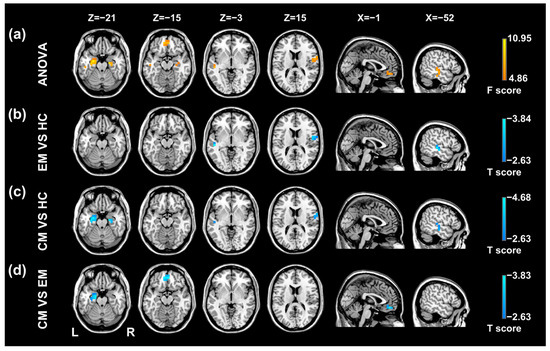

As shown in Table 2 and Figure 2, there were significant lag differences among the groups in the bilateral hippocampus/parahippocampal gyrus (HP/PHG), medial prefrontal cortex (mPFC), right postcentral gyrus/precentral gyrus (PoCG/PreCG), and left superior temporal gyrus/middle temporal gyrus (STG/MTG). Post hoc t-tests demonstrated that the BOLD signal of the mPFC was temporally earlier than the rest of the brain in the CM versus EM group comparison (Table 3, Figure 2). The CM group showed earlier intrinsic activity in the bilateral and left HP/PHG, respectively, when compared with the HC group and the EM group (Table 3, Figure 2). BOLD signals of the left STG/MTG and right PoCG/PreCG were temporally earlier, with respect to the rest of the brain in both migraine groups relative to the HC group (Table 3, Figure 2).

Figure 2. Results of statistical analyses of temporal lag of intrinsic brain activity in the migraine patients and healthy controls. (a) Regions showing significant differences in temporal propagation among the three groups include the left STG/MTG, right PoCG/PreCG, bilateral HP/PHG and mPFC. (b) Temporal propagation differences between the EM group and HC group. (c) Temporal propagation differences between the CM group and HC group. (d) Temporal propagation differences between the CM group and EM group. EM, episodic migraine; CM, chronic migraine; HC, healthy control; STG, superior temporal gyrus; MTG, middle temporal gyrus; PoCG, postcentral gyrus; PreCG, precentral gyrus; HP, hippocampus; PHG, parahippocampal gyrus; mPFC, medial prefrontal cortex.